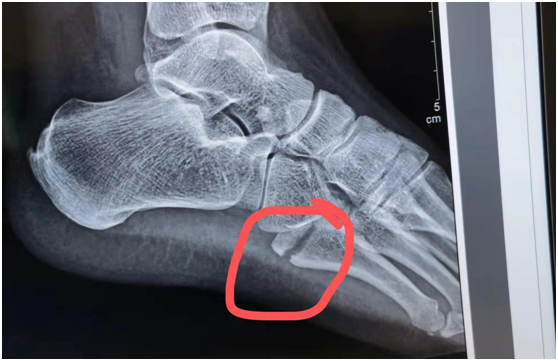

事实上,当天从采样点撤下来,黄恒一身冷汗,回到医院,拍片一看,左足第5趾骨基底部骨折。医生让她马上住院,消肿后手术。如果不马上治疗,会导致脚部肿胀加重、骨折移位,将来可能影响肢体的功能。

3月16日中午,尚剑主任亲自主刀,黄恒在关节创伤科顺利做完左足第5跖骨骨折内固定手术,打入了2枚钢钉。